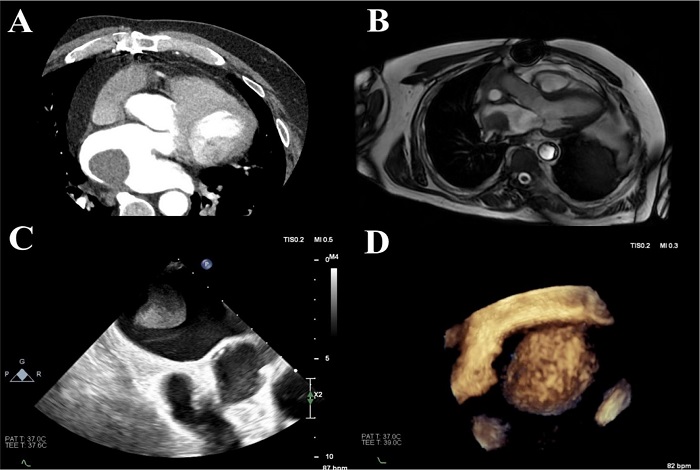

A 60-year-old patient underwent orthotopic heart transplantation in 2008 for end-stage heart failure secondary to dilated cardiomyopathy. The donor heart was from an 18-year-old man who had died as a result of brain injury after a road traffic accident. After heart transplantation, the recipient had two episodes of acute rejection which were treated with pulse steroid therapy, and he was diagnosed with cardiac allograft vasculopathy with non-significant coronary artery disease. Immunosuppression treatment consisted of prednisone, everolimus, and tacrolimus. In 2021, he underwent right nephrectomy due to Grawitz carcinoma. Neither the donor nor the recipient had a family history of cardiac tumors. In the year 2024, in a follow-up echocardiography, a rapidly growing left atrial mass measuring 39 × 28 × 31 mm located at the posterior atrial wall was diagnosed for the first time. Later, the patient underwent multimodality imaging where the diagnosis of left atrial myxoma was established (Figure 1). On the contrary, histology confirmed the diagnosis of organized left atrial thrombus. Based on the preoperative evaluation, the tumor was treated as left atrial myxoma, and the patient underwent urgent redo-surgery with the use of aortobicaval cardiopulmonary bypass. The pedicle of the left atrial tumor was attached to the posterior atrial wall, on the recipient’s site. The tumor was completely excised, and a suture was placed on the tumor’s stalk on the atrial wall (Figures 2A, 2B). The postoperative course was uneventful and on postoperative day eight, he was discharged. Histology examination showed organized left atrial thrombus (Figures 2C, 2D).

Differentiation between thrombus and masses in the atria is challenging. Our case emphasizes the insufficiency of advanced multimodality imaging techniques to provide accurate diagnosis in tumors with features highly suggestive of an atrial myxoma. The patient underwent 3D- transesophageal echocardiography, cardiac computed tomography, and magnetic resonance imaging.